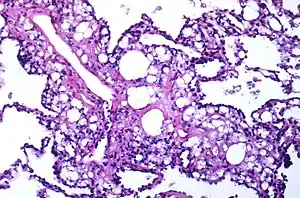

| Numerous interstitial fat globules of varying size accompanied by inflammation and fibrosis is characteristic of chronic lipid pneumonia secondary to lipid aspiration. | |

Once inhaled, these fuels induce an inflammatory reaction in lung tissue. They are not metabolized by tissue enzymes, but undergo emulsification and become engulfed by macrophages which, with time, may disintegrate and release oily substances surrounded by fibrous tissue and giant cells.[8]